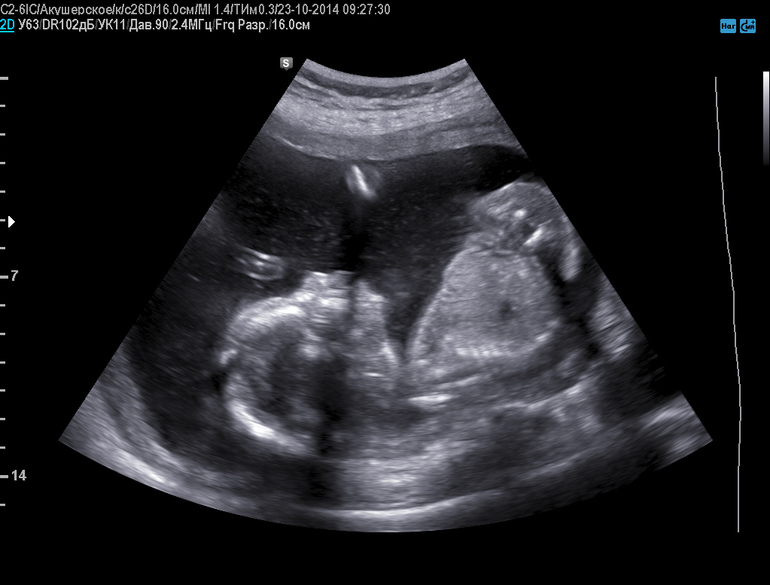

2-й скрининг

Вот и прошла я второй свой скрининг, мой мальчик подтвердился, только я теперь не плакала, а улыбалась) Свыклась полностью с этой мыслью, все хорошо! Тем более и имя у него уже есть - Ярослав!